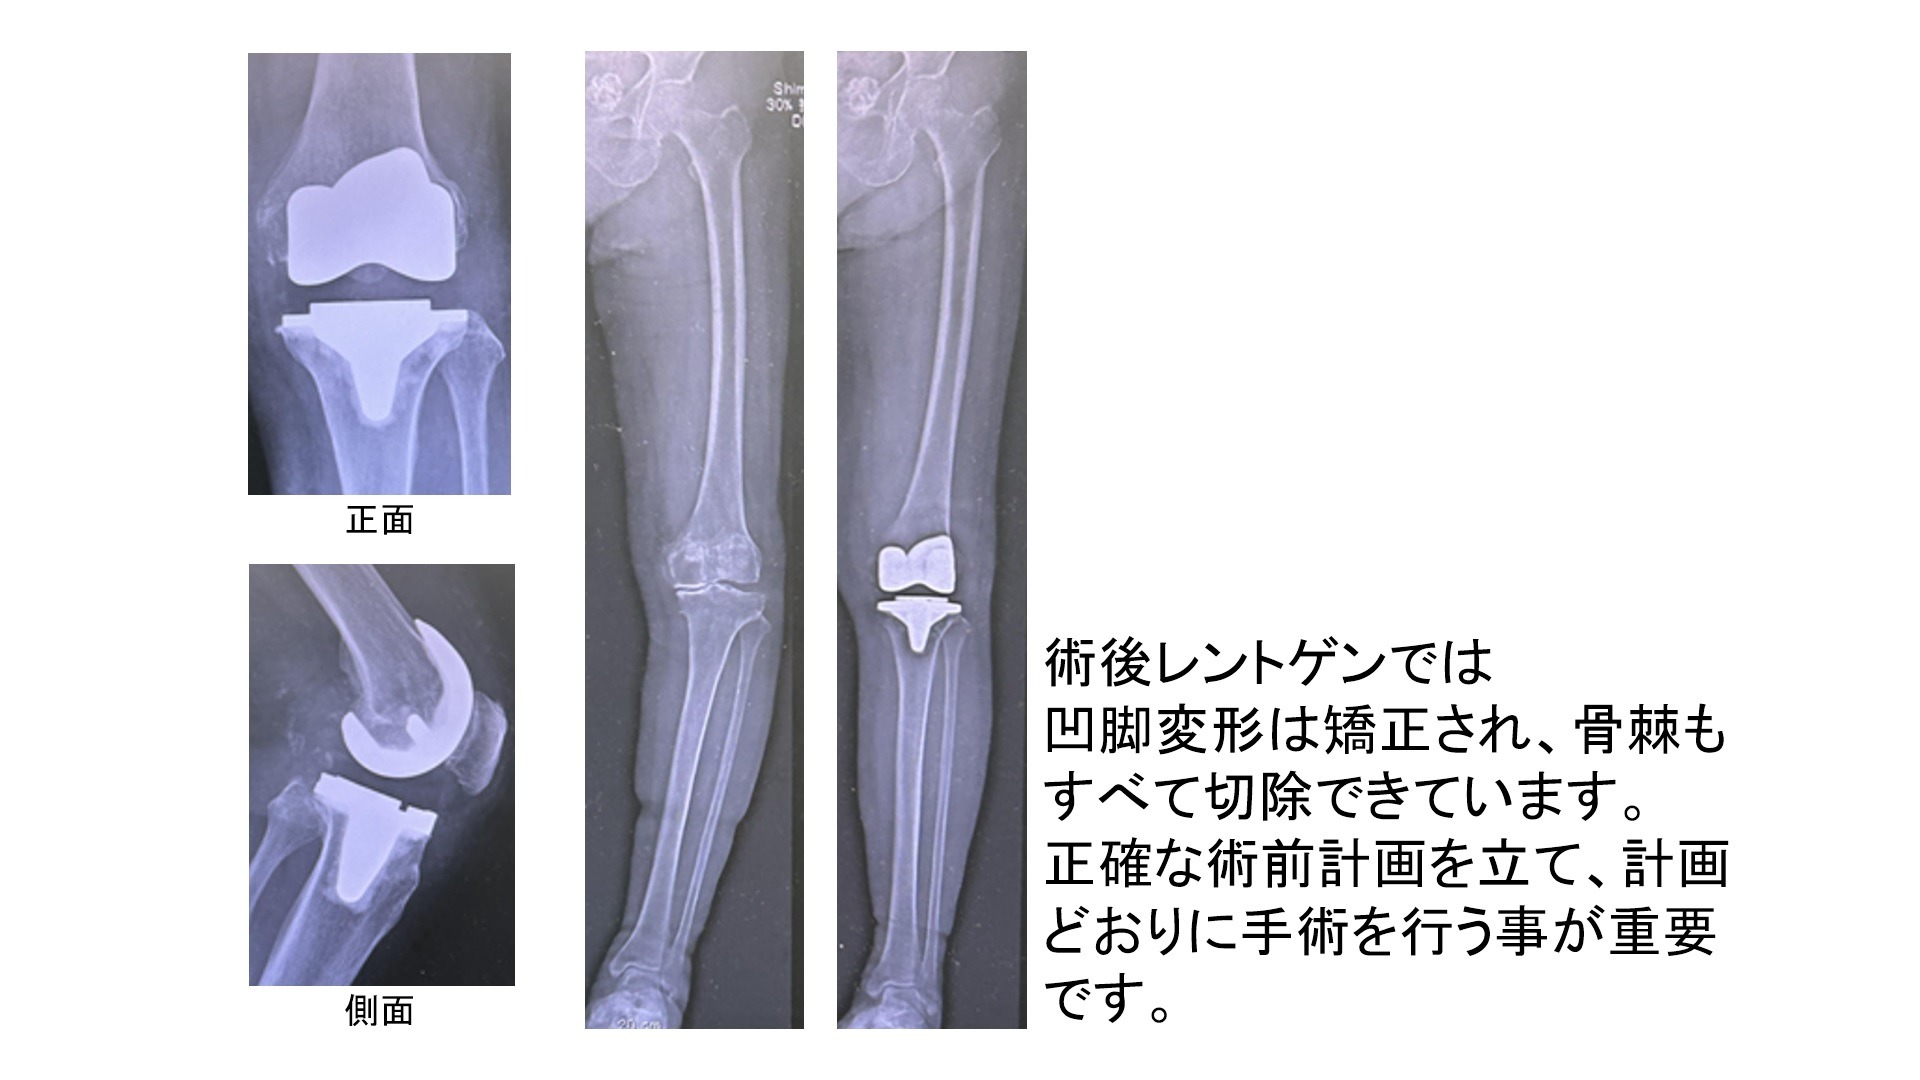

2.人工膝関節

変形した膝関節を再建するために1950年台にイギリスで開発され進化を遂げてきました。現在は大腿骨側で痛んだ骨を削ってコバルトクロム製の大腿骨インプラントを設置し、脛骨(すねの骨)側で痛んだ骨を削ってコバルトクロム製の脛骨インプラントを設置します。それらの間に軟骨の代わりになるインサート(高分子ポリエチレン)を設置して手術を終了します。変形の状態や疾患によっては膝蓋骨側もインプラント(高分子ポリエチレン)で置換する場合があります。

①CTを用いた三次元手術計画(LEXY社3次元術前計画支援ソフトを使用)を行います

患者さんごとに適切な人工関節の大きさ、形状、位置などを正確に決定することができます。

②同日に両側人工膝関節置換術の施行が可能です(3~4週ほどで自宅退院)

両側同時手術の場合、片側ずつ2回手術するより入院期間が短縮できるメリットがあります。

当院では関節周囲カクテル注射で疼痛コントロールを、トラネキサム酸という止血剤で出血コントロールを行っているため、両側同時手術にも関わらず輸血を行わずに施行できております。